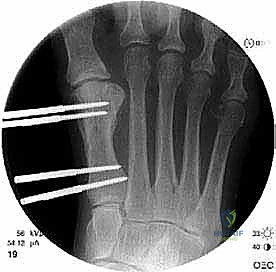

الخطوة الثالثة: قص العظم (Osteotomy)

باستخدام منشار جراحي ميكروسكوبي دقيق، يقوم الدكتور هطيف بقص عظم مشط القدم. تعتمد زاوية وشكل القص (مثل القص المائل أو القص على شكل حرف Z) على مقدار الإطالة المطلوبة وشكل العظم المتبقي من الجراحة السابقة.

الخطوة الخامسة: التثبيت الداخلي القوي (Internal Fixation)

لضمان التئام العظم في وضعه الجديد والطويل، يجب تثبيته بقوة شديدة. يستخدم الدكتور هطيف أحدث الشرائح المعدنية التيتانيوم ذات الزاوية الثابتة (Locking Plates) والمسامير الدقيقة. هذا التثبيت القوي يمنع أي حركة بين العظام ويسمح ببدء العلاج الطبيعي في وقت مبكر.